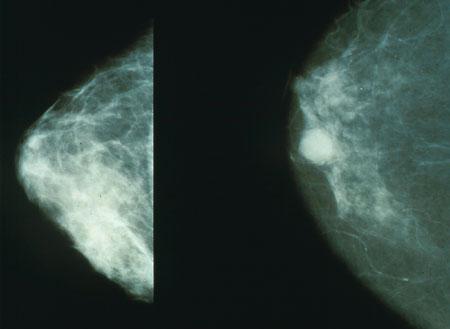

Poza Mamaografie

Mamografia digitala

Mamografia reprezinta o interventie radiologica cu raze Roentgen a sanului. Se foloseste ca metoda principala pentru depistarea precoce a cancerului de san (carcinom mamar), cea mai frecventa forma de cancer la femeie in majoritatea tarilor.

Investigatia se efectueaza cu un aparat Roentgen special, asa numitul mamograf. Acesta utilizeaza o radiatie Roentgen cu energie scazuta.

Mamograful poate fi analogic cu filme ce se developeaza sau digital. Mamograful digital trimite imaginile sanului pe un ecran special dedicat pentru astfel de investigatii. Imaginile mamografice captate digital pot arhivate si imprimate pe un CD sau film.

Mamografia curativa ofera o posibiltate de diagnosticare in plus in cazul unei suspiciuni de tumoare (un nodul palpabil sau o secretie la mamelon).